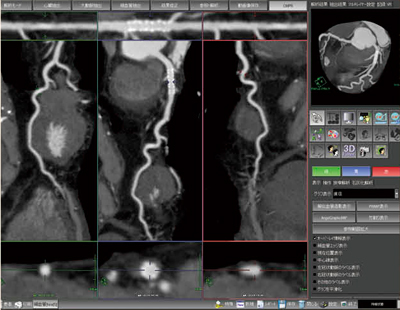

改良された冠動脈解析用ソフトウェアCT細血管解析は,より臨床に即したアプリケーションとなっている。自動解析の精度も向上し,さまざまな症例に対応可能となっている。観察に使用する画面は,さらに使いやすくレイアウトを変更できるようになっており,新たに3枝を同時表示できるレイアウトが追加された(図2)。これにより,画面を切り替えることなく複数の枝を同時に観察することが可能となり,3枝病変の観察や側副血行路などの観察が容易に行えるようになっている。

図2 冠動脈3枝同時解析画面